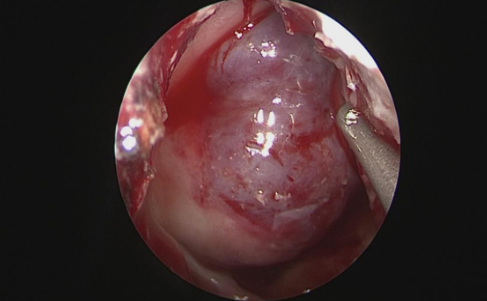

(神经内镜下充分显露鞍底)

患者为中年藏族男性,39岁,一年前因垂体瘤在四川大学华西医院西藏成办分院行经额部开颅垂体瘤切除术,术后复发遂到昌都市人民医院外二科就诊。在昌都市人民医院党委、外二科余正强主任以及重庆市“组团式”医疗援藏队的大力支持下,现任外二科副主任的重医大附二院神经外科陈晋副教授带领张琪医生,围绕神经内镜辅助下经鼻蝶窦垂体肿瘤切除的适应症、具体操作及术后护理康复等方面,在科室全体医护人员参与下进行了充分讨论并制定了详细的预案。经过周全准备,在昌都市人民医院麻醉科余中良主任、来自重庆三峡中心医院麻醉科的援藏队员陈吕富副主任亲自施行麻醉下,陈晋副教授与张琪医生顺利进行了神经内镜辅助下经鼻蝶入路垂体肿瘤切除术,术中全切肿瘤,出血约50ml。护理团队积极指导康复训练,术后仅七天患者便康复出院。